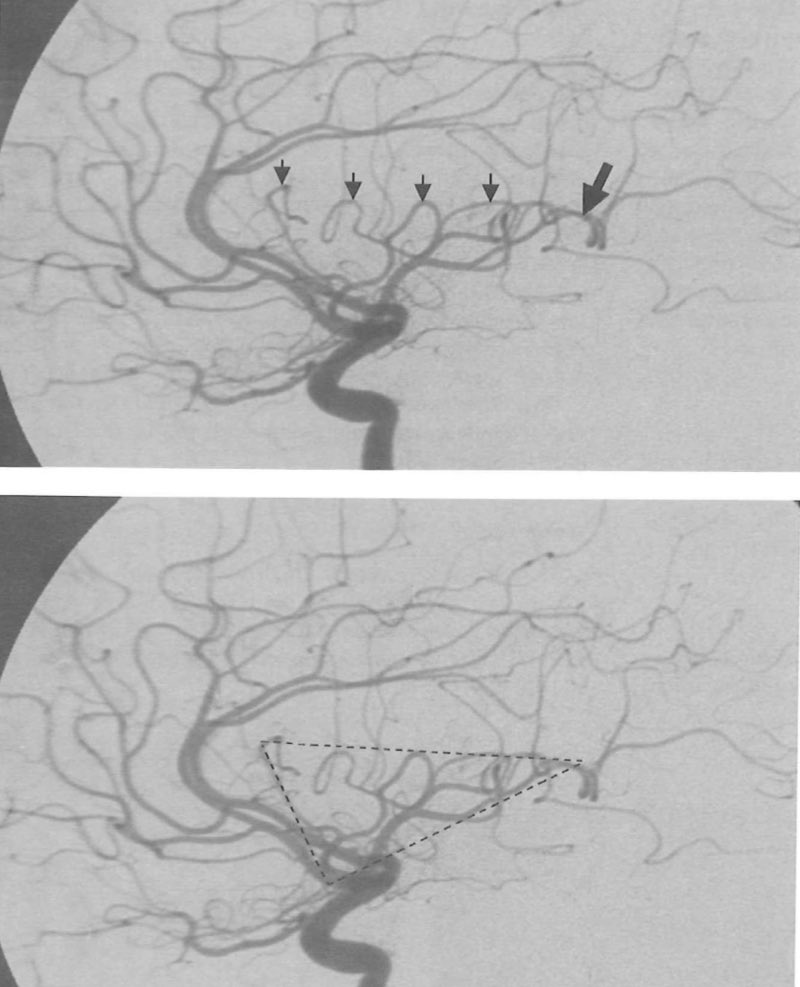

درايف يضم كل ملخصاتي لجراحة المخ والأعصاب 🧠

Devoted to Neurosurgery @KFMC_Riyadh , driven by teaching , but not everyone can pick up a scalpel and be extraordinary.